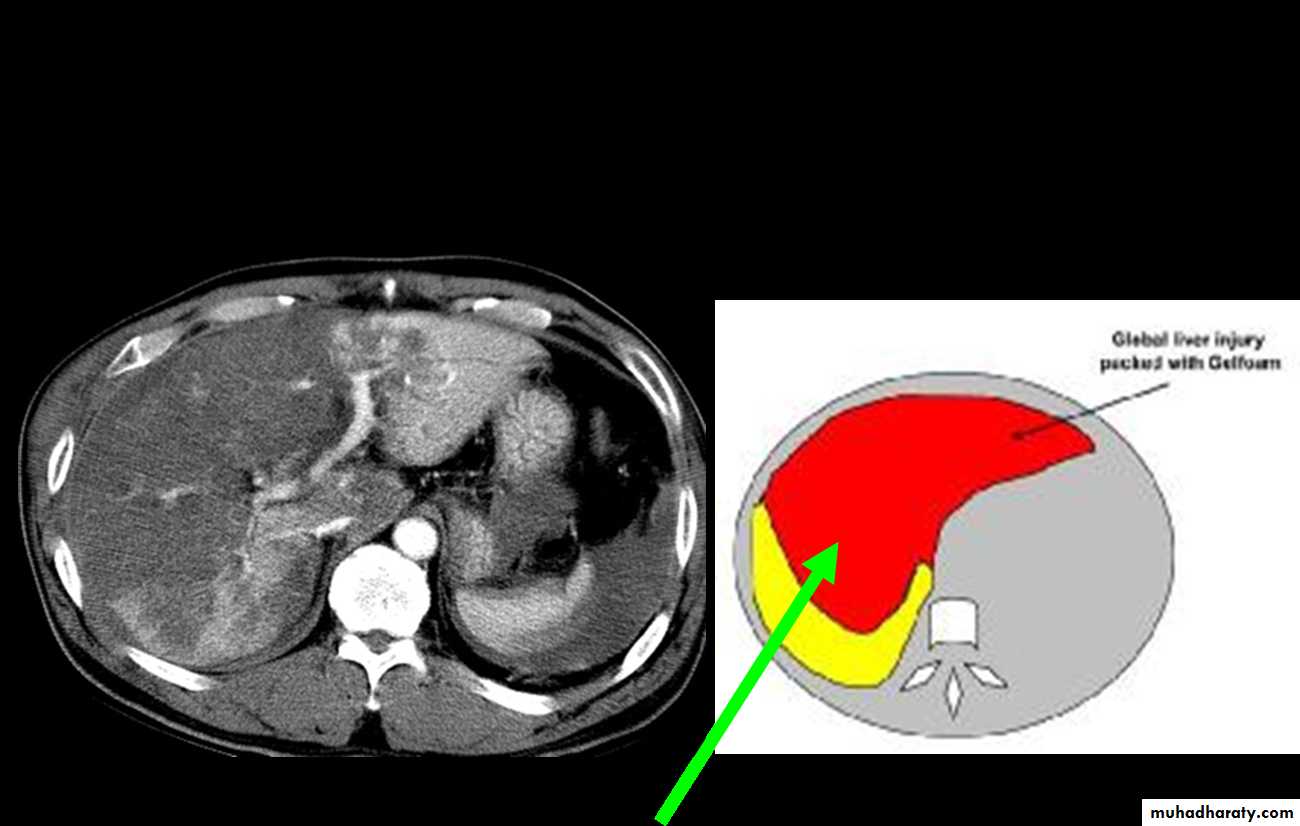

CT Scans

Accurate in localizing the site of liver injury and any associated injuries

Used to monitor healing

CT criteria for staging liver trauma uses AAST liver injury scaleGrades 1-6

Classification(AASTI-Subcapsular hematoma<1cm, superficial laceration<1cm deep.